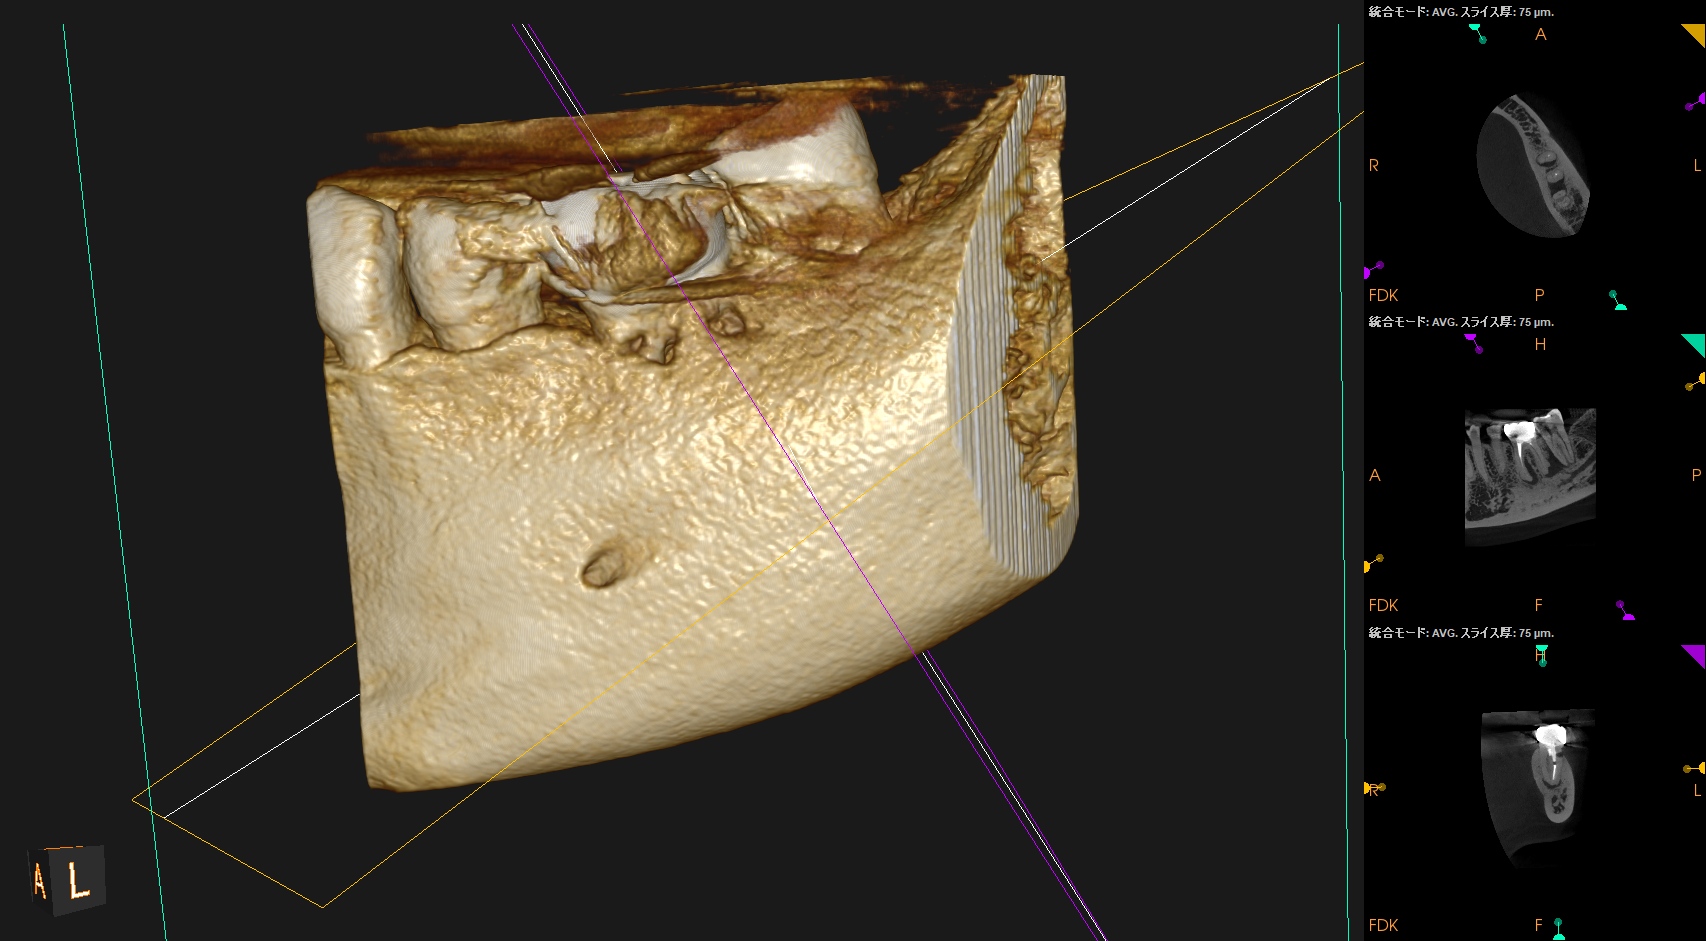

前回、前々回の記事で歯内療法におけるCBCTの有用性について論じたが、

今日はその応用編をご紹介する。

穿孔しているのだろうか?とまず思ったが、CBCTをみてそれは穿孔でなく外部吸収の可能性が高いと判断できた。

もはや全ての歯内療法の処置前には必ずCBCTが必要

という法則が成り立つ。

これらの画像的事実と臨床検査から

1. まず外部吸収を封鎖する

2. その後(その日に)、再根管治療を行う

という治療計画を提示し、患者さんが同意していただいたのでまずは外科だ。

術後にPA, CBCTを撮影した。